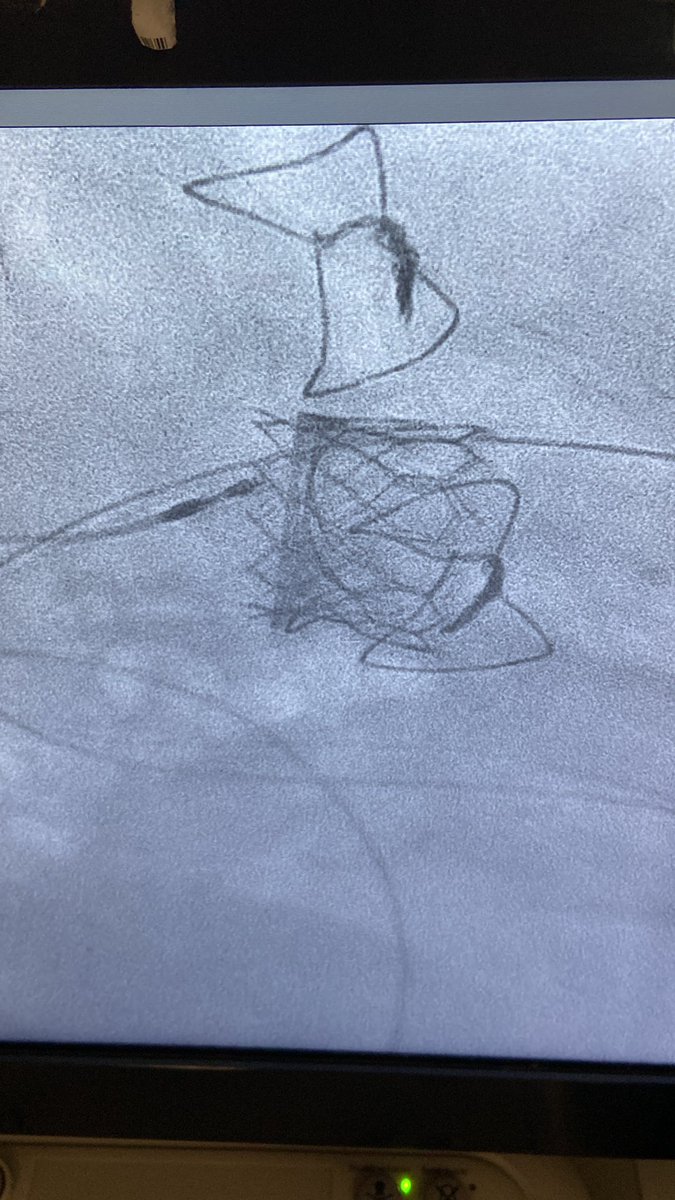

Congratulations Dr Saber Hassan and team @materprivate on first #Navitor #TAVI #TAVR in Ireland 🇮🇪 @AbbottNews

Well done to the excellent Charleroi, Belgium team for 3 quality Navitor implants in edge of the envelope Anatomy👏